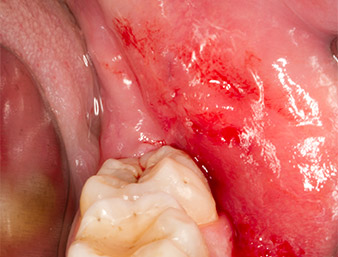

Nach Leitungs- und Lokalanästhesie wurde das Operationsfeld für einen bukkal-retromolaren Zugang weichgewebig eröffnet und dargestellt (Abb. 3).

Das Gewebe über dem Wurzelrest war nicht vollständig verknöchert und bestand zu einem großen Teil aus entzündlich verändertem Granulationsgewebe (Abb. 4).